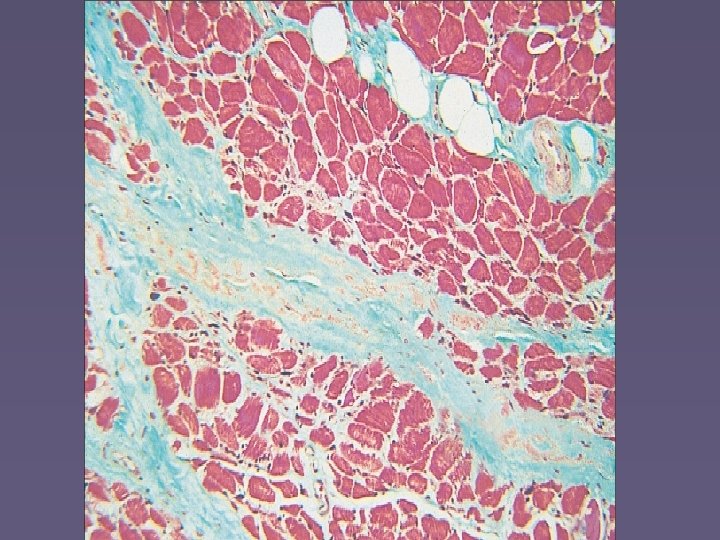

Chronic dermatomyositis